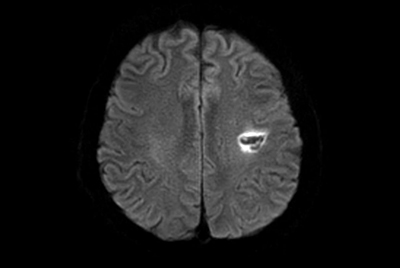

Multiple Sclerosis versus TIA

Brain Multiple Sclerosis

FLAIR* protocol for Multiple Sclerosis

Brain infarction

Brain small infarction